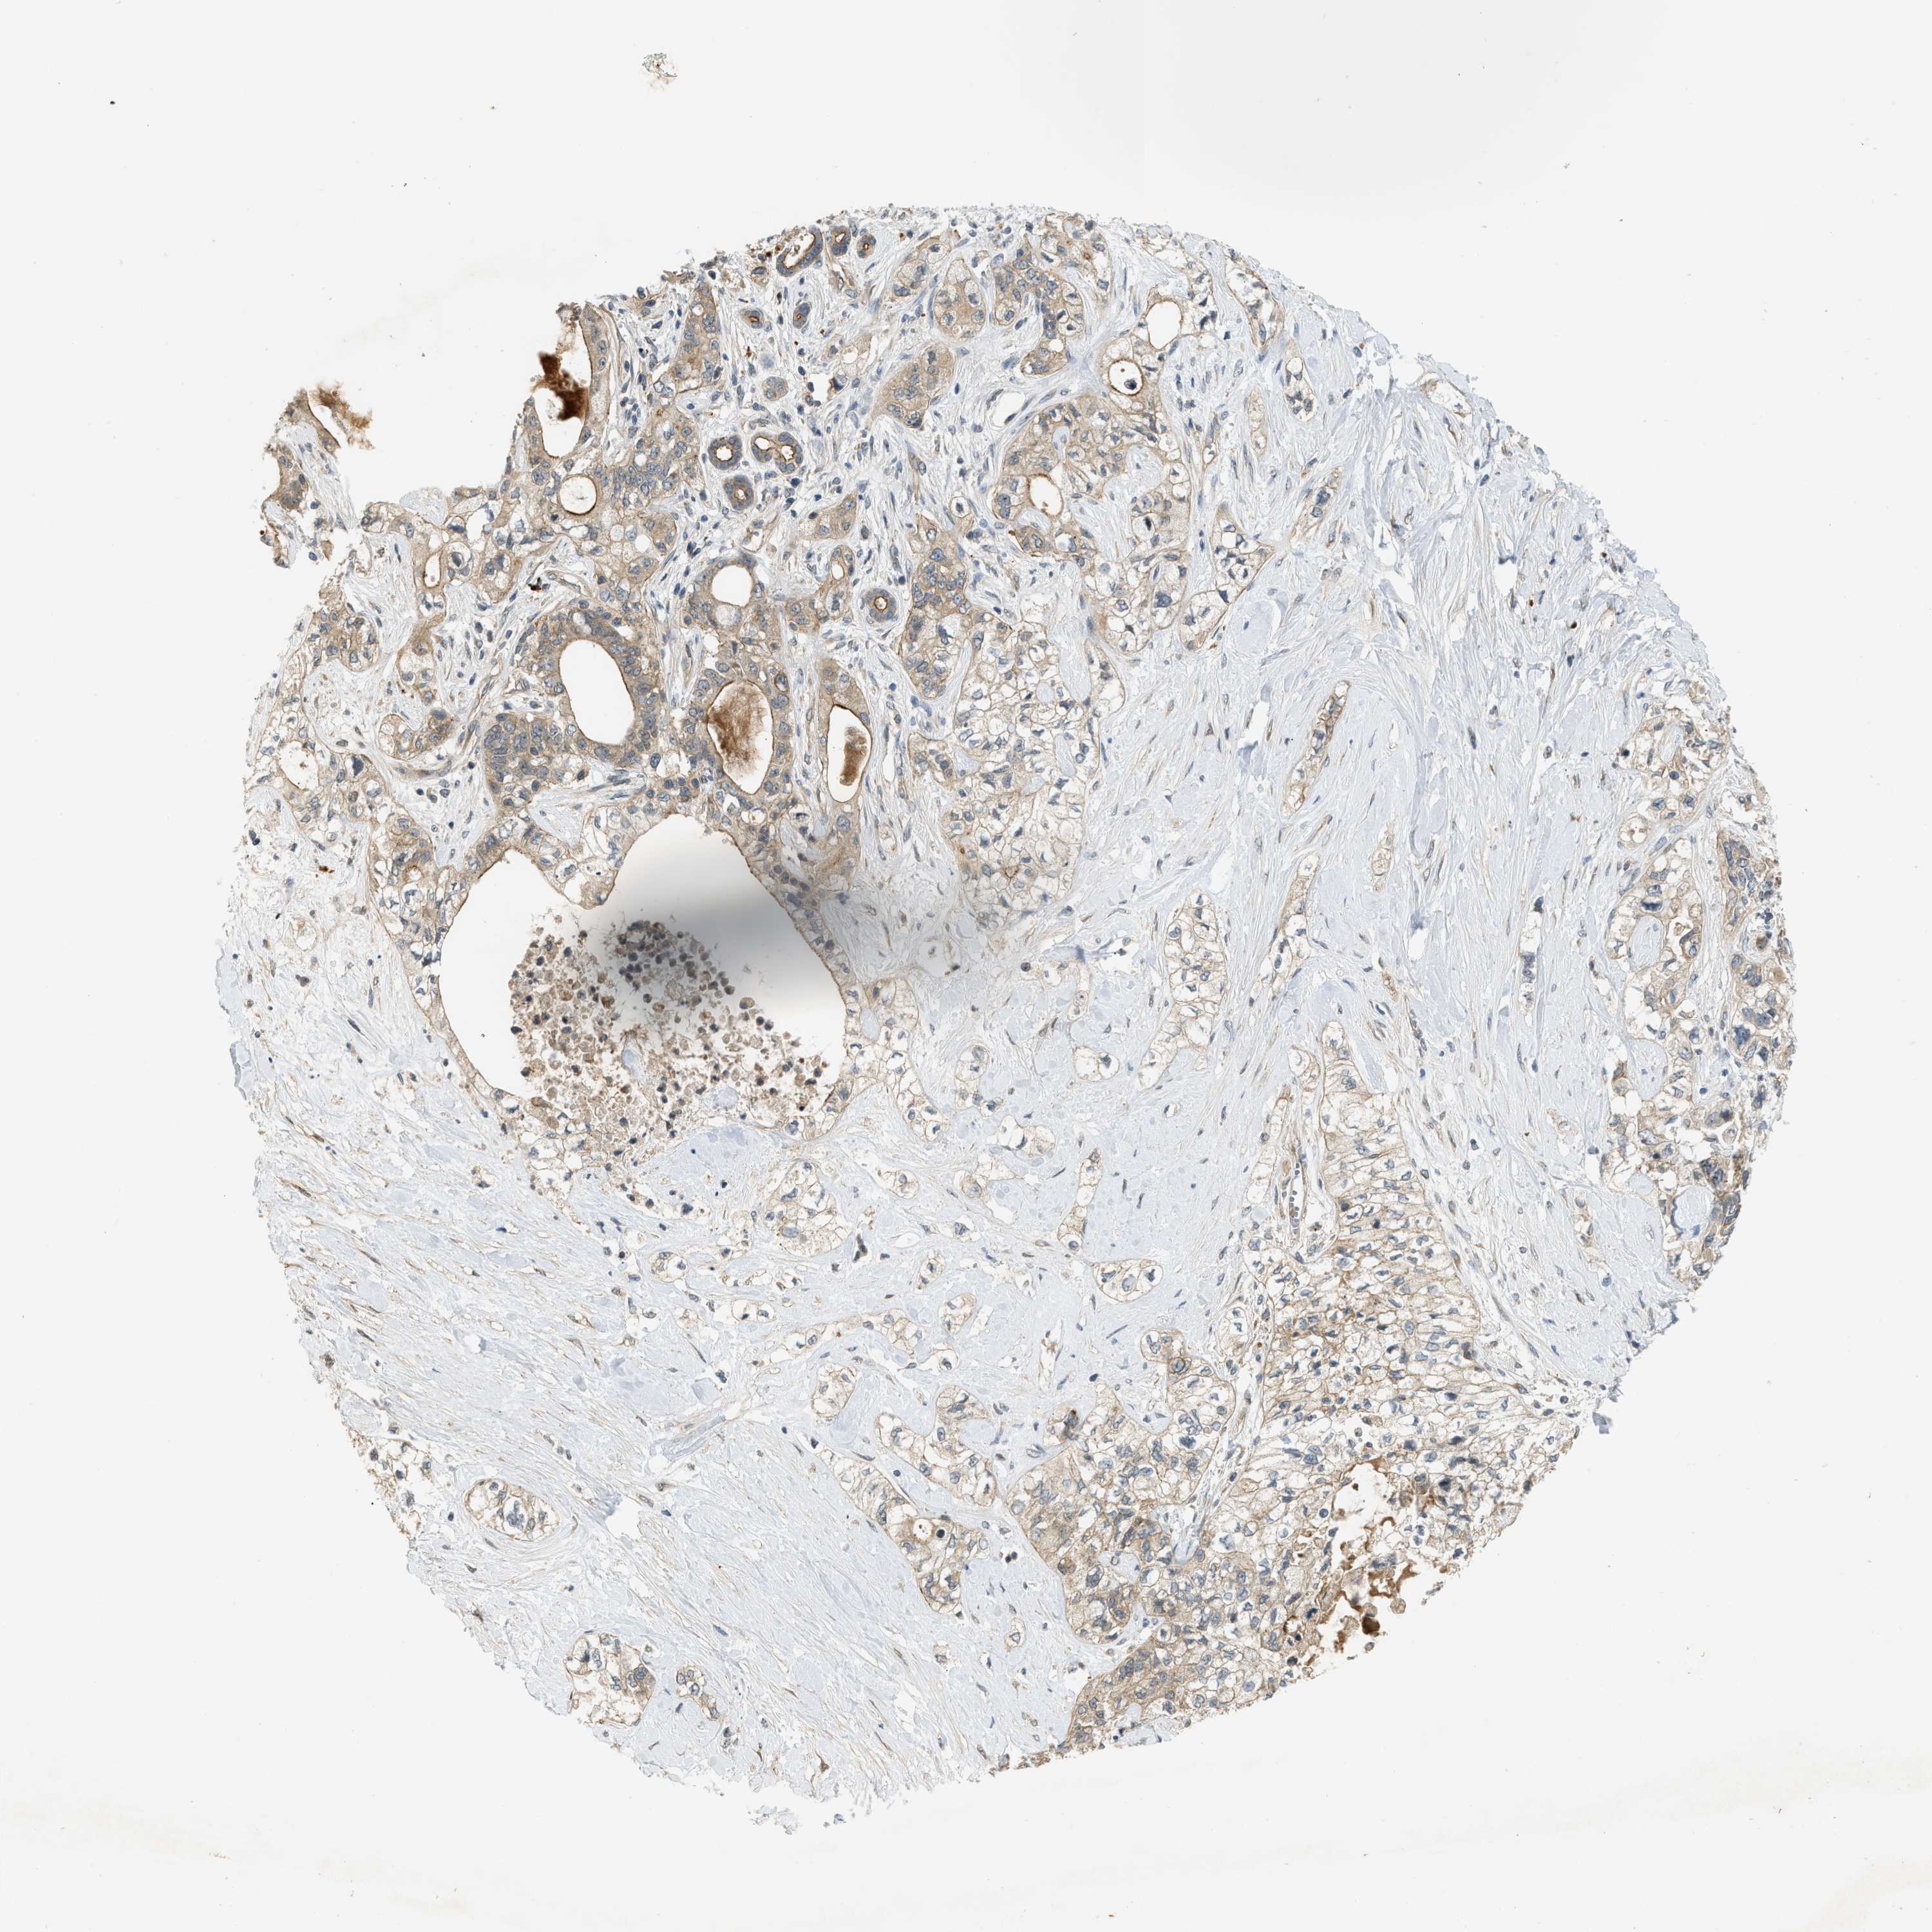

PANCREATIC CANCER - Protein expressioni

A mouse-over function shows sample information and annotation data. Click on an image to view it in a full screen mode. Samples can be filtered based on level of antibody staining by selecting one or several of the following categories: high, medium, low and not detected. The assay and annotation is described here.

Note that samples used for immunohistochemistry by the Human Protein Atlas do not correspond to samples in the TCGA dataset.

Antibody stainingi

Antibody staining in the annotated cell types in the current human tissue is reported as not detected, low, medium, or high, based on conventional immunohistochemistry profiling in selected tissues. This score is based on the combination of the staining intensity and fraction of stained cells.

Each image is clickable and will lead to virtual microscopy that enables deeper exploration of all samples and also displays staining intensity scores, fraction scores and subcellular localization as well as patient and tissue information for each sample.

Antibody HPA024291

Antibody CAB018652

Staining

High

Medium

Low

Not detected

Intensity

Strong

Moderate

Weak

Negative

Quantity

>75%

75%-25%

<25%

None

Location

Nuclear

Cytoplasmic/membranous

Cytoplasmic/membranous,nuclear

Adenocarcinoma, NOS